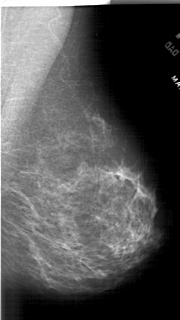

A_1905_1.RIGHT_MLO

RIGHT_MLO LINES 5746 PIXELS_PER_LINE 3226 BITS_PER_PIXEL 12 RESOLUTION 43.5 NON_OVERLAY